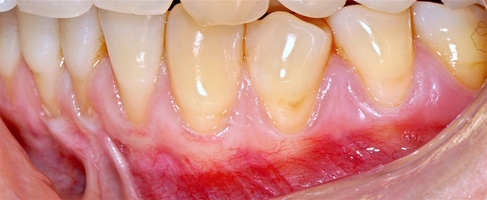

Во всех случаях применения аутотрансплантата и ТМО (dura mater) наблюдается сопоставимый положительный клинический результат по всем параметрам оценки рецессий десны (табл. 4). В случае нескольких зубов в области наиболее глубоких рецессий с наименьшими клиническими показателями имеет место сохранение класса рецессии не более первого класса (9 зубов) и глубиной не более 2 мм, 1.6 зуб — 3 мм.

В зарубежной литературе встречается также совокупный показатель эффективности лечения рецессий десны — процент закрытия корня зуба — отношение разница между конечным и исходным значениями глубины рецессии к исходному значению в процентах. Положительный результатом лечения является значение равное или более 80% [4]. Использование только показателя глубины рецессии десны для анализа эффективности лечения без учета остальных показателей (ТКД, ШКД, РРД, ЗДК) не дает полной картины результата и может быть применимо только в совокупности с другими показателями (рис. 6а-й).

Так в нашем случае процент закрытия корня зуба наблюдается больше 80% у 13 зубов. Менее 80% — у 11 зубов. Это связано с сохранением класса рецессии после лечения в области зубов с наибольшим классом рецессии и наибольшим показателем глубины рецессии. При этом средний показатель всех 24-х оперированных зубов — 83,1%. При этом среднее значение процента закрытия корня зуба для зубов с положительным результатом (более 80%) составляет 96,65%. Среднее значение для результатов менее 80% — 54,73, что связано с изменением глубины рецессий с 6 мм до 3 мм, с 4 мм до 2 мм и с 2 до 1 мм. При этом для аутотрансплантата и для ТМО результаты сопоставимы.

Через 12 месяцев (рис. 7а-г) на срезах компьютерной томограммы 11-ый и 13-ый зубы находятся в костной ткани, при этом костные пики и перегородки укрепились, объем их увеличился; вестибулярно заметен объем костной массы, предположительно компактной формации, исходя из электронной плотности участка. Этим объясняется отсутствие рецидива при лечении рецессии десны как в случае применения аутотрансплантата, также и ТМО (dura mater).